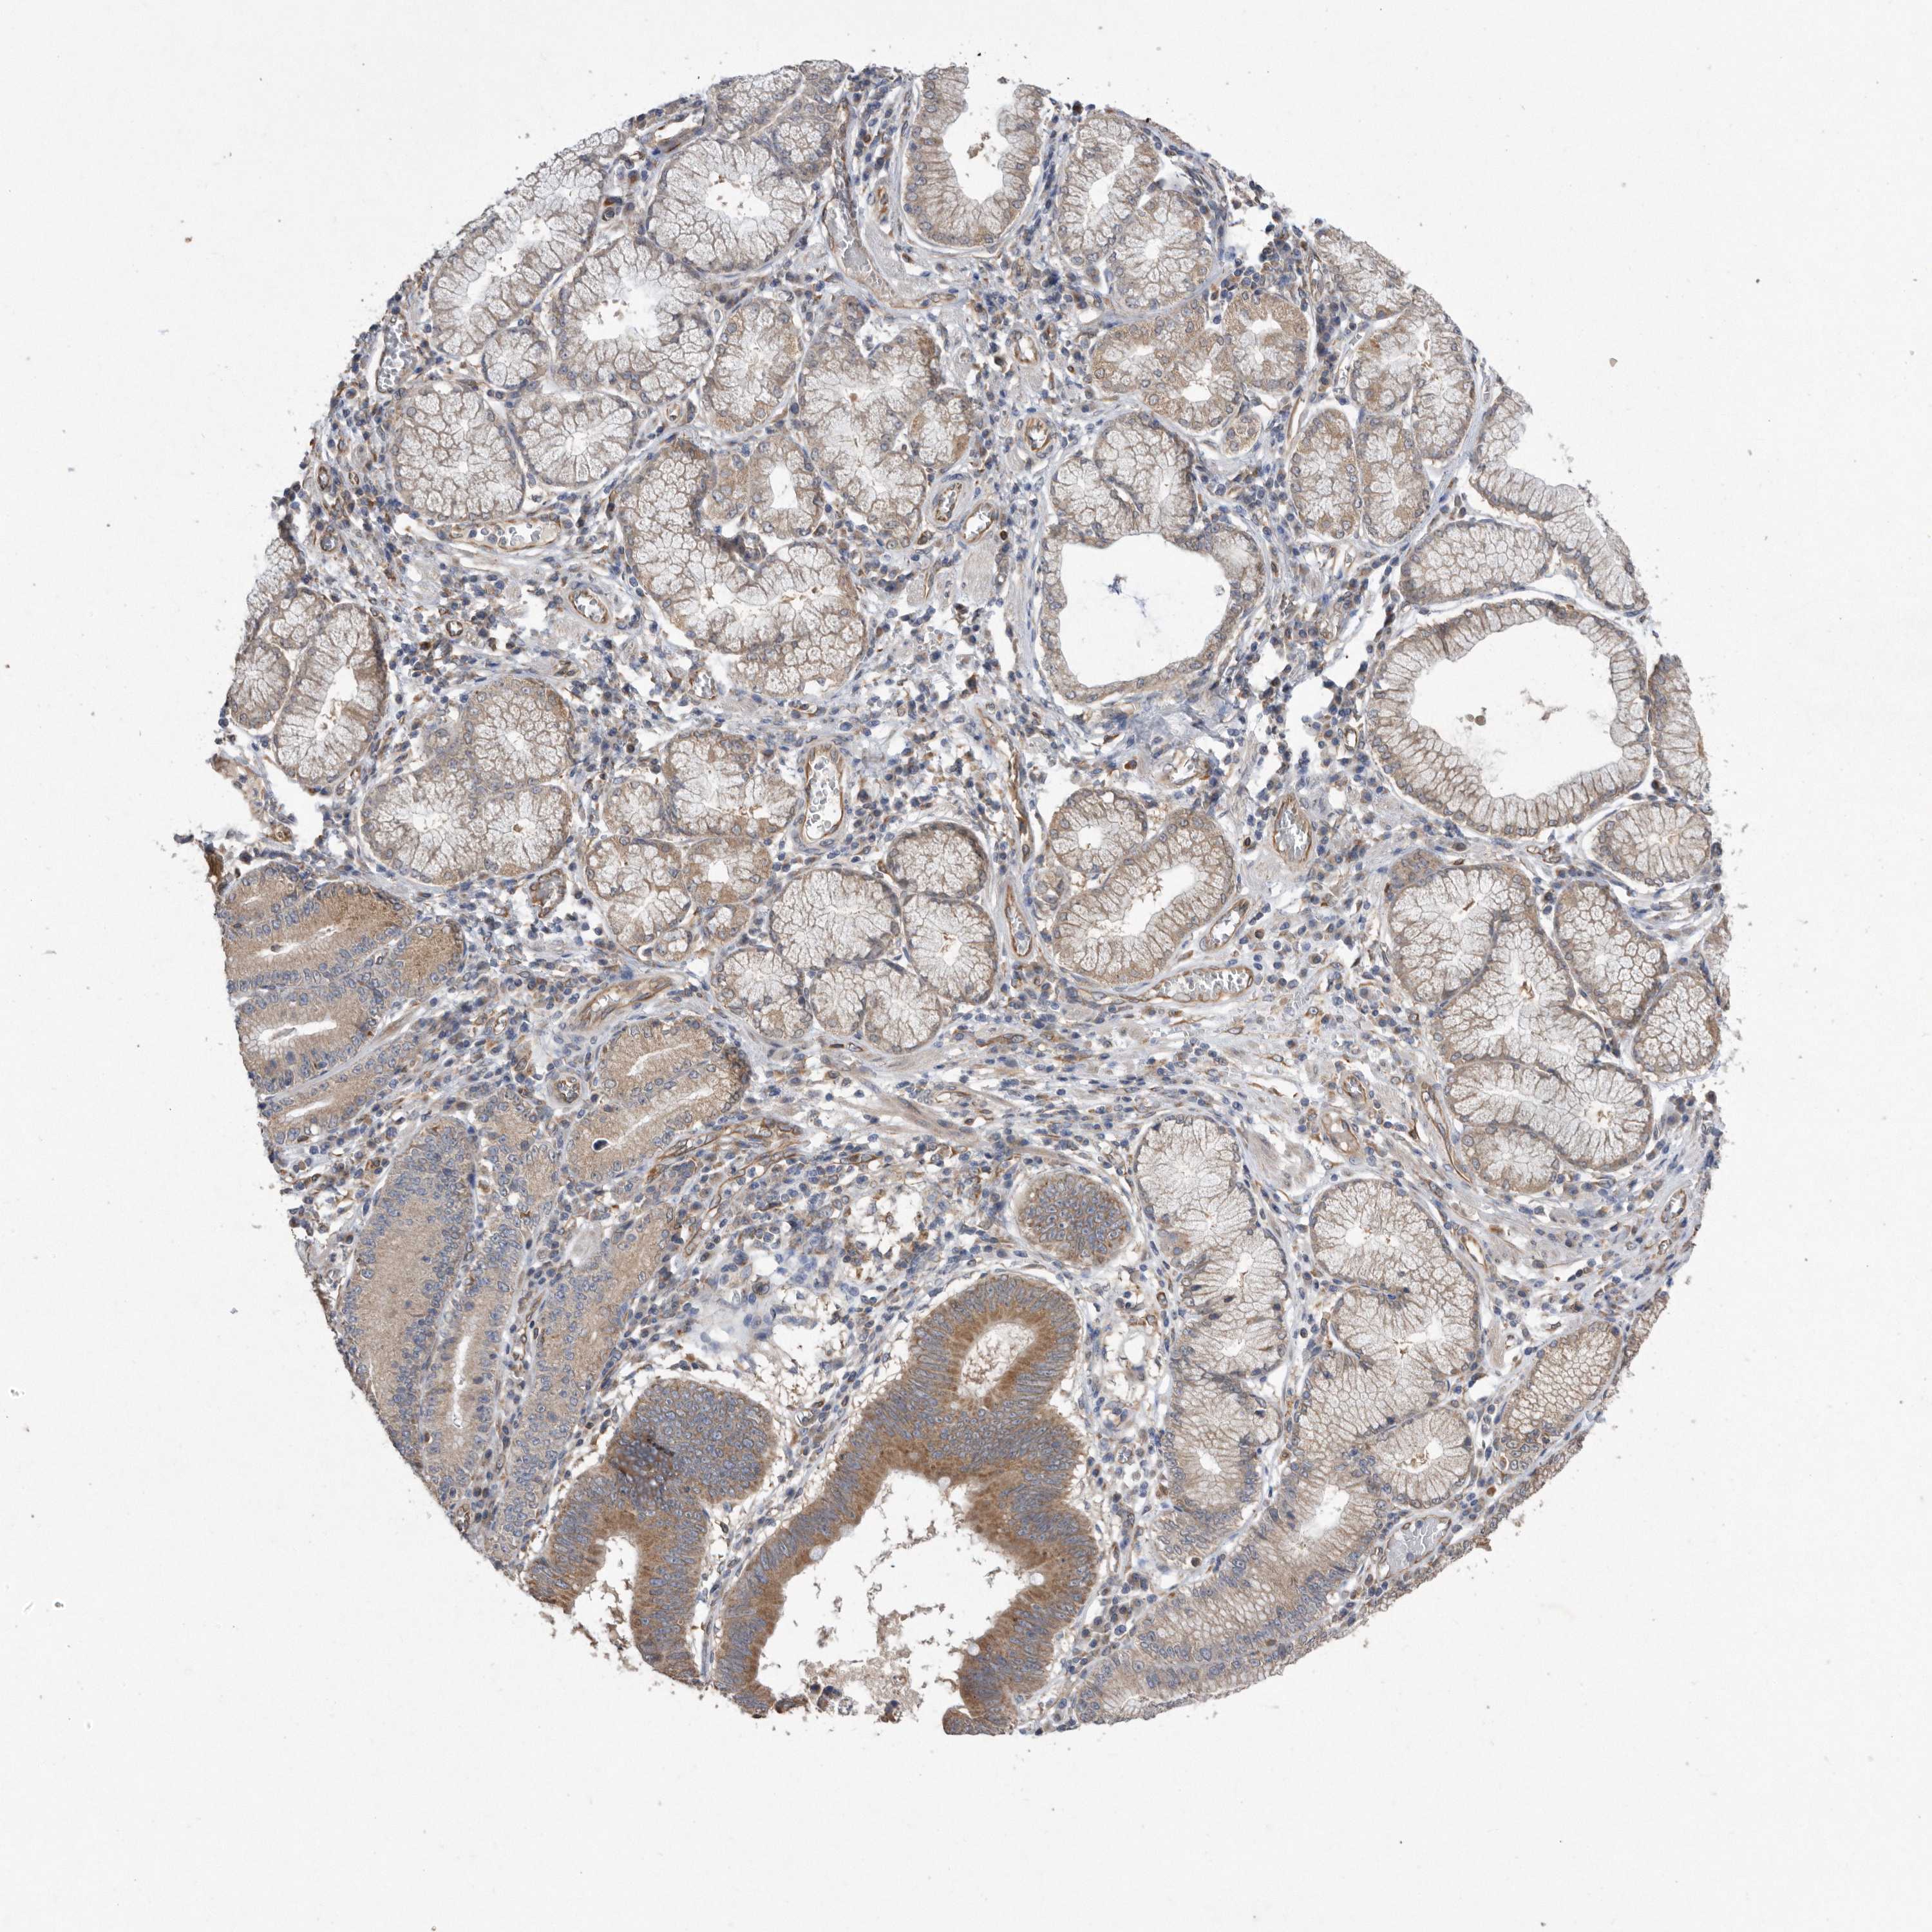

STOMACH CANCER - Protein expressioni

A mouse-over function shows sample information and annotation data. Click on an image to view it in a full screen mode. Samples can be filtered based on level of antibody staining by selecting one or several of the following categories: high, medium, low and not detected. The assay and annotation is described here.

Note that samples used for immunohistochemistry by the Human Protein Atlas do not correspond to samples in the TCGA dataset.

Antibody stainingi

Antibody staining in the annotated cell types in the current human tissue is reported as not detected, low, medium, or high, based on conventional immunohistochemistry profiling in selected tissues. This score is based on the combination of the staining intensity and fraction of stained cells.

Each image is clickable and will lead to virtual microscopy that enables deeper exploration of all samples and also displays staining intensity scores, fraction scores and subcellular localization as well as patient and tissue information for each sample.

Antibody HPA029193

Antibody CAB025430

Staining

High

Medium

Low

Not detected

Intensity

Strong

Moderate

Weak

Negative

Quantity

>75%

75%-25%

<25%

None

Location

Nuclear

Cytoplasmic/membranous

Cytoplasmic/membranous,nuclear

Adenocarcinoma, NOS

Adenocarcinoma, High grade